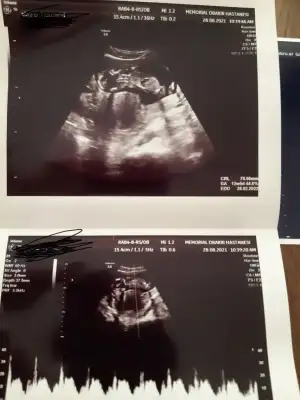

dr soylemeden siz gorun genital nub teorisi ( bebegin cinsiyeti)

MerhabaNet değil o nedenle yazmadım başka USG varsa paylaşın 10-11-12-13

Evet kız Gibi görünüyor

Erkek sanki emin olamadım başka USG varsa paylaşın

Biraz aşağısıIkra meyra nub işaretlemişim yer mı oluyor canım

Evet bende emin olamadım12 haftalık doktor kız gibi dedi ama yanılma çok oluyor dedi 1 ay sonra netleştirirz dedi bazen pipilerini göremiyoruz dedi çok ufak olduğu için yanılabilriz dedi

Bizde bugün kontrolden çıktık 12+3 haftalığız ,doktor cinsiyet için emin olamadı resimlerden siz yorum yapabilirmisiniz

Bu hafta da nub yanıltır cnm en iyi 11 12 13 haftalar olmalıIkra meyra gözükmüyor o zaman değil mi bu ultrasonda

Tamam çok teşekkürlerBu hafta da nub yanıltır cnm en iyi 11 12 13 haftalar olmalı